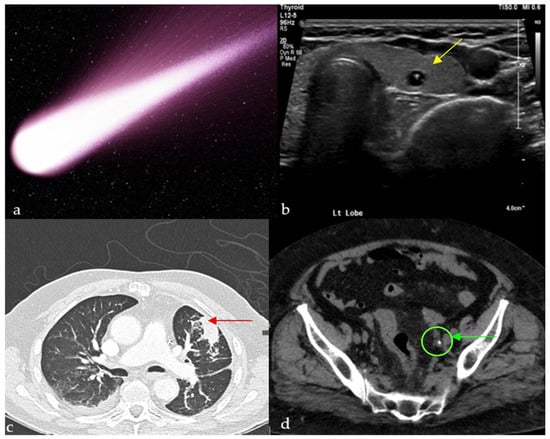

Cosmic Signs in Radiology: A Pictorial Review

Pattern recognition remains a cornerstone of radiologic interpretation, as it facilitates a confident and comprehensive differential diagnosis. Certain pathologies present with specific and highly recognizable patterns on imaging modalities. These patterns can resemble familiar real-life phenomena, including cosmic bodies that surround us. We present in this article a compilation of radiologic signs across various modalities that take inspiration from cosmic phenomena. For each sign, we summarize its defining imaging appearance, typical clinical context, and common pitfalls; where available, we note diagnostic performance (e.g., sensitivity/specificity) to guide appropriate weighting in practice. By coupling memorable imagery with succinct clinical guidance, this pictorial review aims to support a faster, more accurate pattern recognition that is applicable in both low-resource and tertiary care settings, while recognizing that these signs function as educational aids rather than validated diagnostic tests. In familiarizing themselves with these classic signs, training radiologists can benefit from an engaging and memorable way of recognizing various pathological conditions. Full article

Figure 1